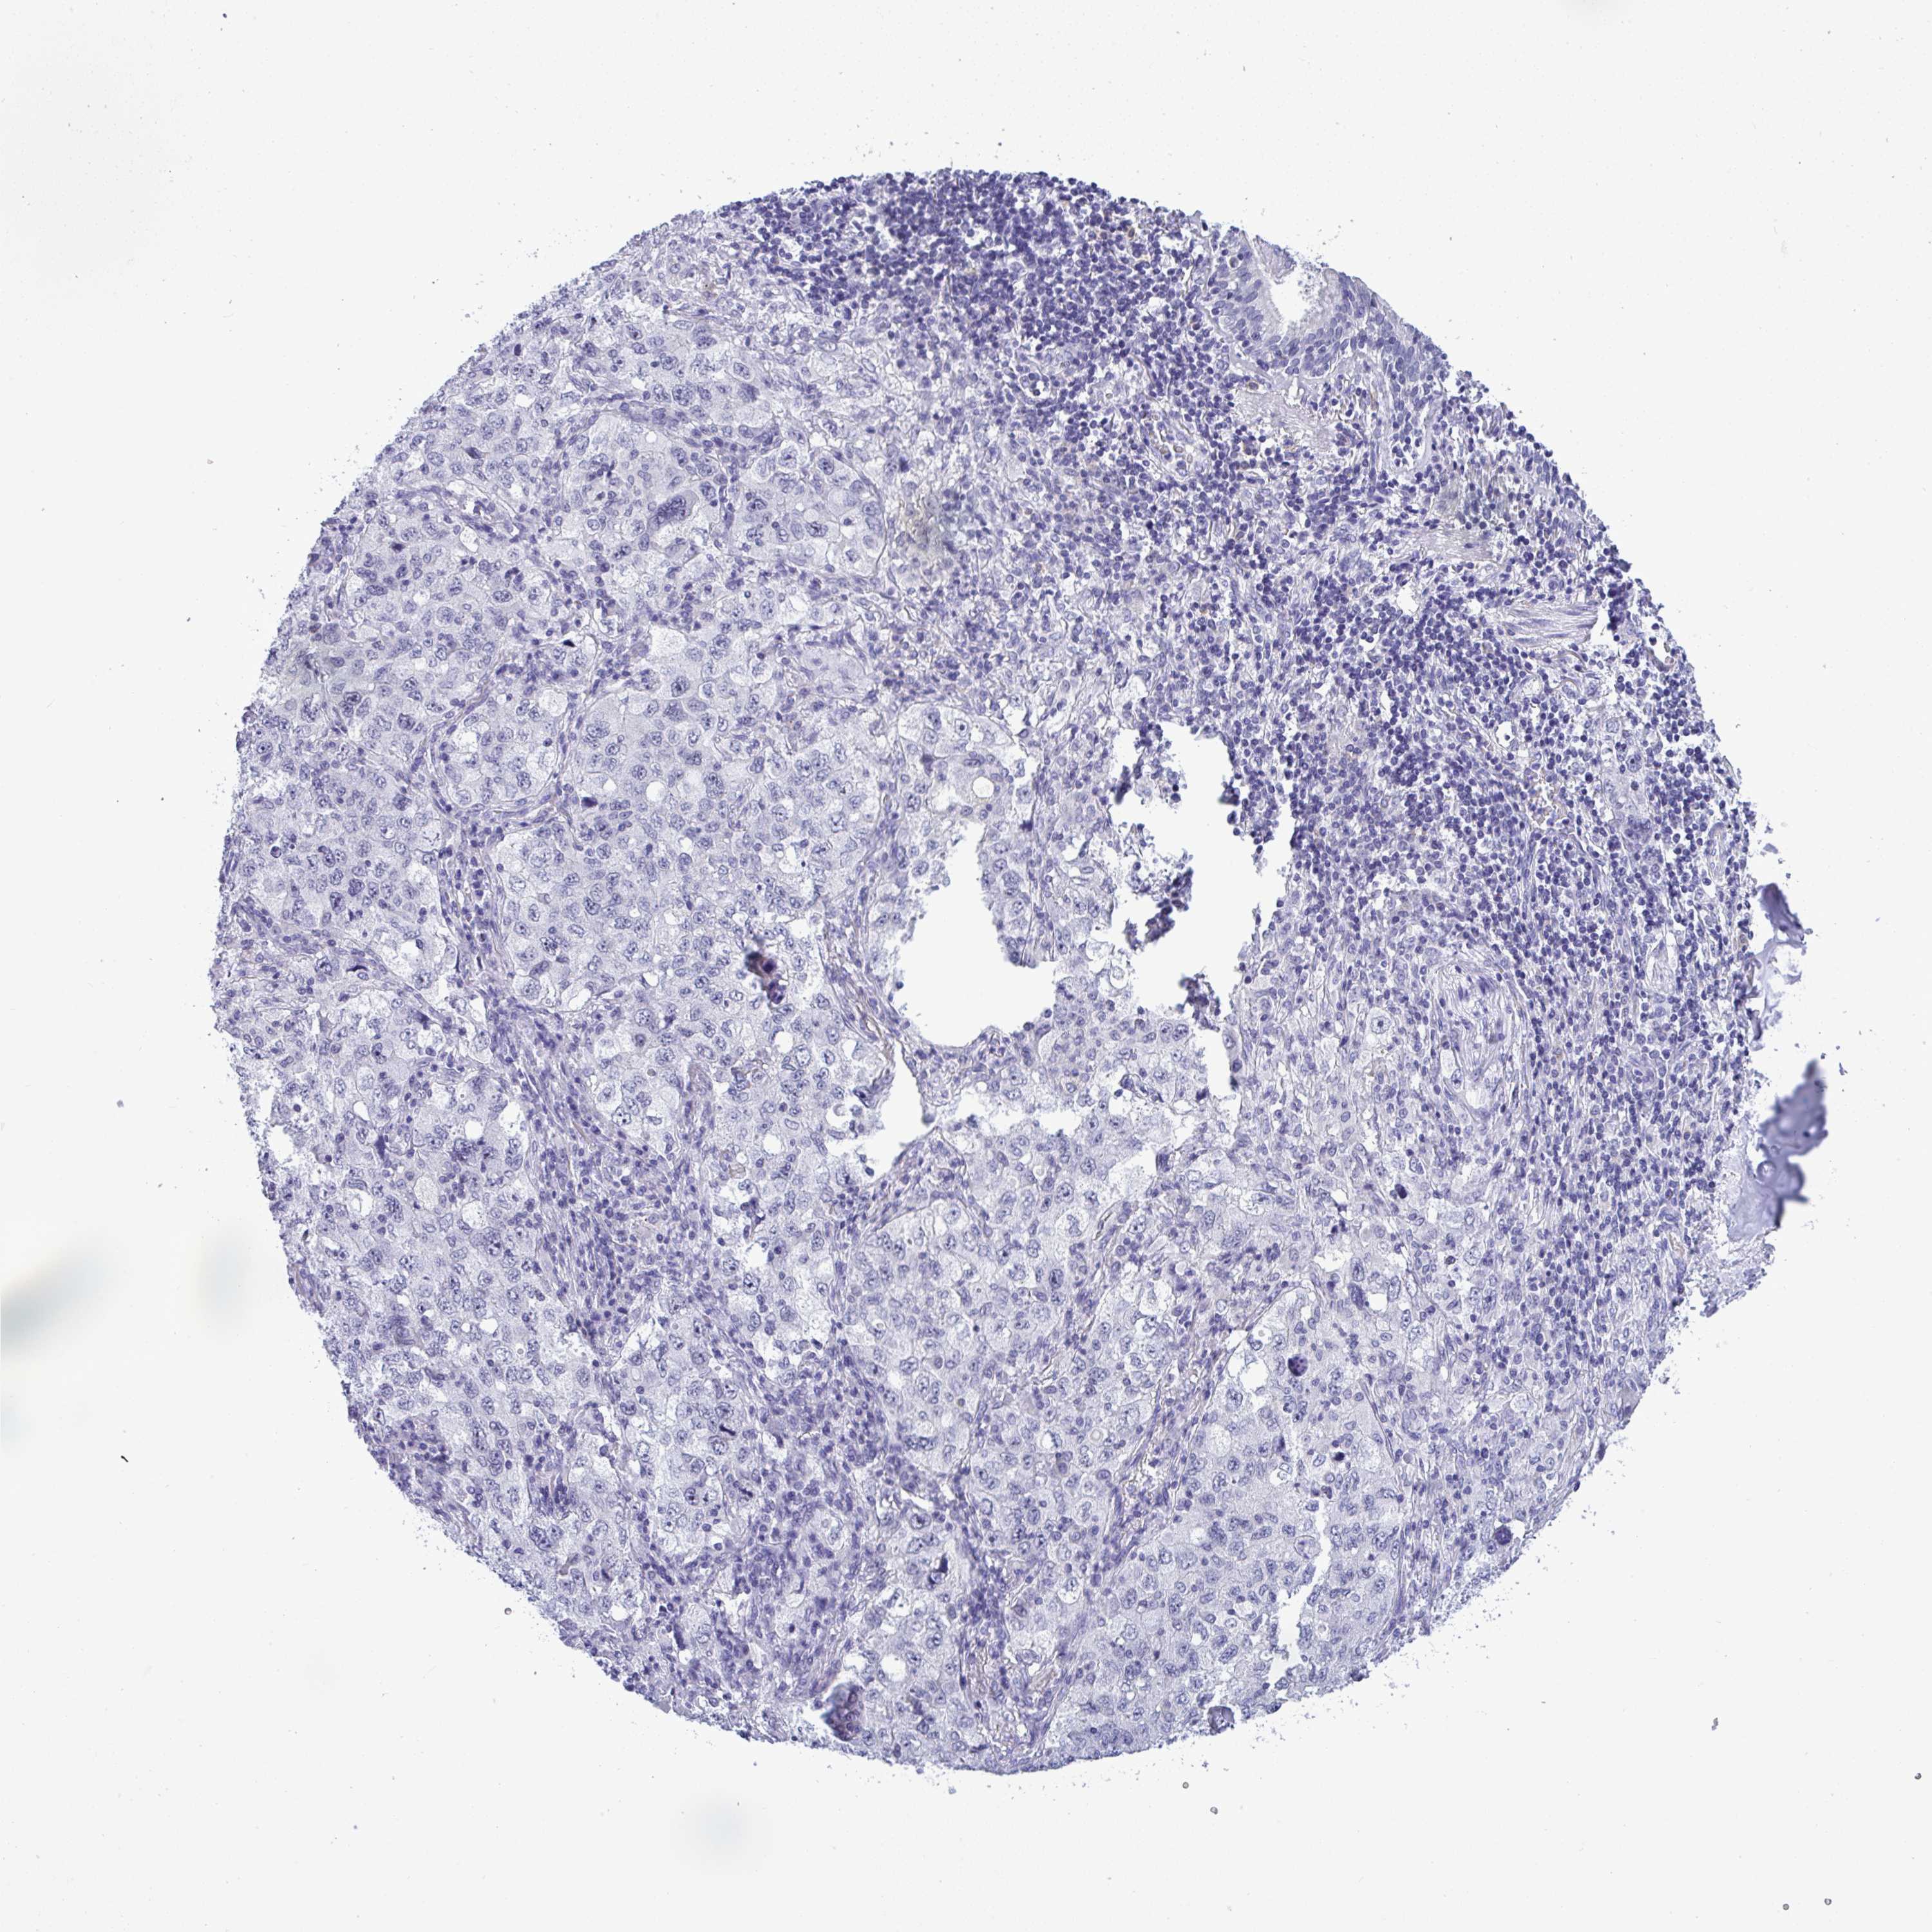

LUNG SQUAMOUS CELL CARCINOMA (TCGA) - Interactive survival scatter ploti

YBX2 is not prognostic in Lung Squamous Cell Carcinoma (TCGA)

: 0.89

Average pTPM 1.1

Number of samples 489